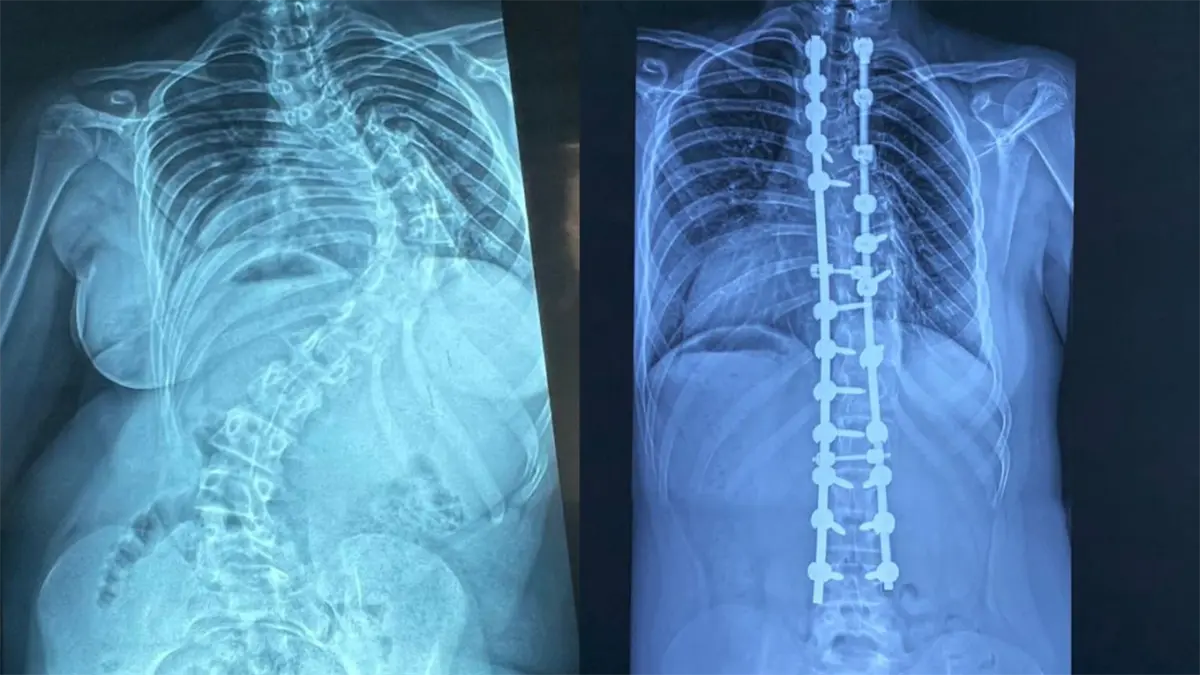

Realizan cirugías deformidades columna pediátrica para mejorar calidad de vida.

La escoliosis es una desviación de la columna vertebral mayor de 15 grados. El especialista detalló que la forma más frecuente es la idiopática del adolescente.

Advirtió que, cuando progresa, puede comprometer órganos vitales.

"Es una patología que básicamente va a mermar la calidad de vida de los pacientes, porque esas desviaciones que continúan progresando durante el crecimiento pueden comprimir órganos internos como el corazón y los pulmones", explicó.

Sobre los resultados, destacó que muchos pacientes intervenidos hoy llevan una vida normal.

"Después de una cirugía como esta pueden hacer su vida prácticamente normal, en igualdad de condiciones que cualquier otro niño".